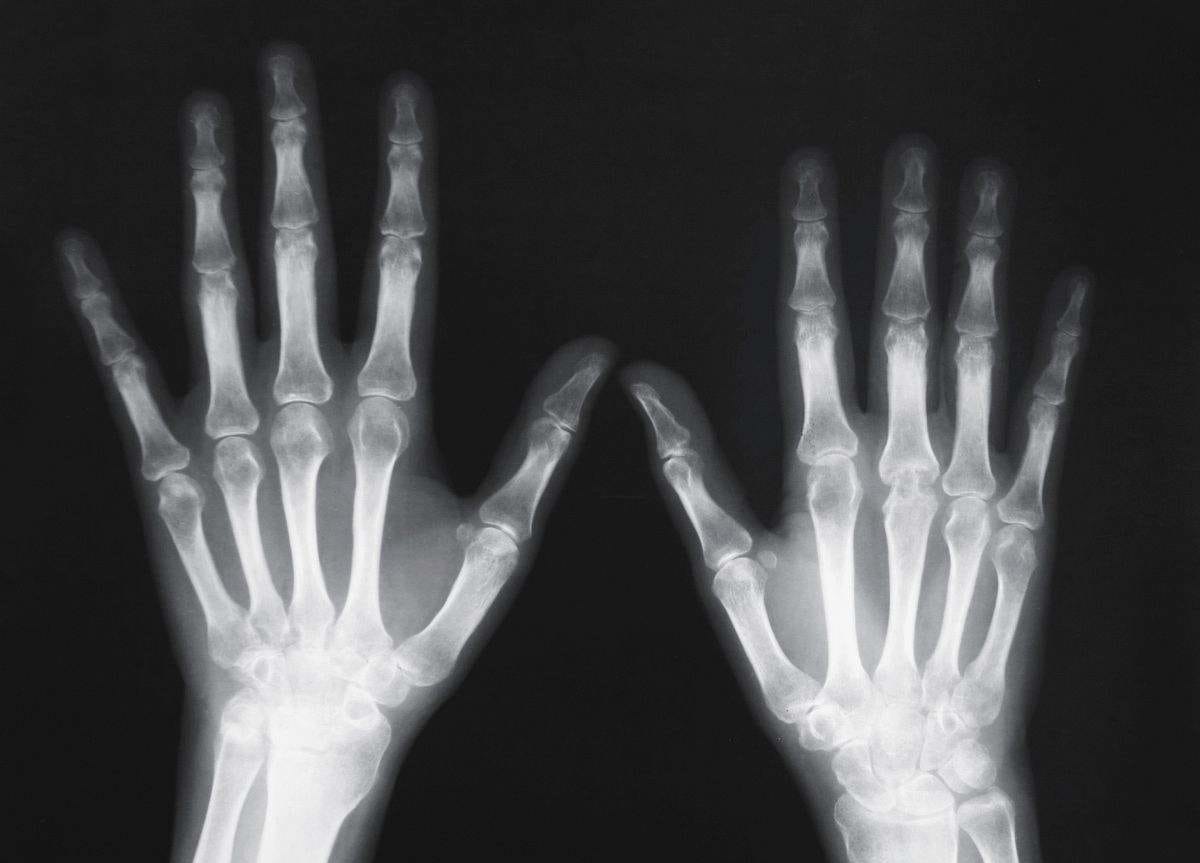

医学影像学——X线

X线检查作为辅助检查方法之一。临床医学上常用的X线检查方法有透视和摄片两种。

摄片能使受检部位结构清晰地显示于X线片上,并可作为客观记录长期保存,以便在需要时随时加以研究或在复查时作比较。必要时还可作X线特殊检查,如断层摄影、记波摄影以及造影检查等。选择何种X线检查方法,必须根据受检查的具体情况,从解决疾病(尤其是骨科疾病)的要求和临床需要而定。X线检查仅是临床医学辅助诊断方法之一。